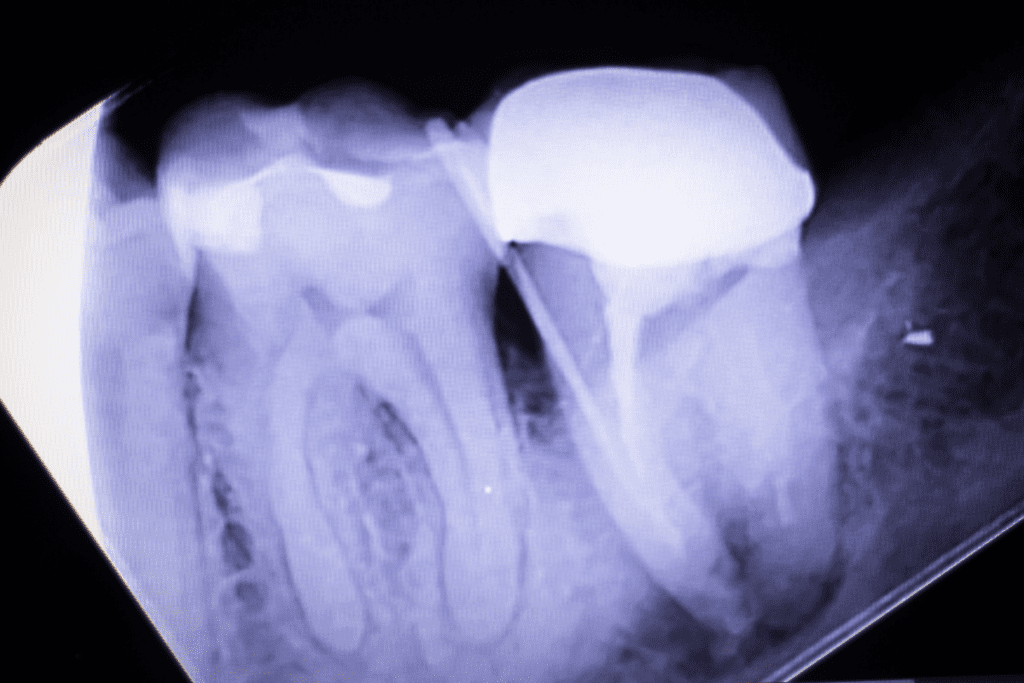

The cavity deepens as bacteria penetrate the dentin layer (the softer tissue beneath enamel). The infection continues towards the pulp chamber, where your tooth’s nerve and blood vessels sit. As bacteria invade the pulp, it becomes inflamed and irritated. At this stage, antibiotics won’t stop the infection; you need professional intervention. Root canal treatment becomes the primary option to save your tooth.

At tooth abscess stage 3, the infection has now created a collection of pus at the tooth’s root. This abscess is your body’s attempt to wall off the infection and prevent it from spreading further. However, the pressure from this pus buildup is what causes the intense pain. The abscess may remain contained at the root tip (periapical abscess) or form between the tooth and gum (periodontal abscess). Either way, the pocket won’t drain on its own and requires professional treatment to resolve. This is when we typically recommend urgent root canal therapy or, if the tooth is beyond saving, extraction.

This is the abscess type you’ve likely read about in the earlier tooth abscess stages. It forms at the tip of the tooth’s root after infection spreads deep into the pulp. The abscess sits in the bone directly beneath your tooth, which is why you experience intense throbbing pain and facial swelling. It’s the most common type because it develops from the inside out, making early detection difficult. At Pure Dental, we typically address periapical abscesses with root canal treatment. The good news: if caught at Stages 2-3, we can save your natural tooth through endodontic therapy. Waiting until Stage 4 often means extraction becomes necessary.

X-rays help us see decay between teeth and below the gum line. Professional cleaning removes tartar buildup that brushing can’t eliminate. We also screen for gum disease, which is a major abscess risk.